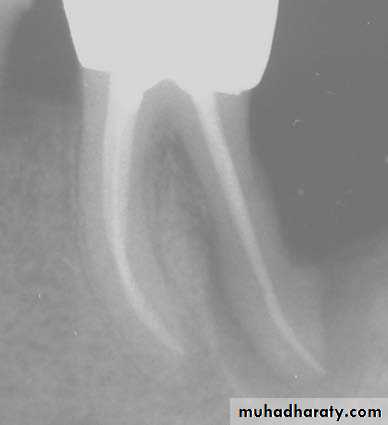

*The No. and curvature of root canals may need modification of outline form & to avoid scarifying of tooth structure.2.Preoperative radiograph: Give great information about status, shape and size of pulp chamber.

Radiographs in Endodontics*Initial radiograph: Diagnosis. *Working length film: Used to determine the length of the canal. *Final instrumentation film: Taken with the final size files in all canals. *Root canal completion film: Taken after the tooth as been temporized. *Recall films: Taken at evaluations.

Requirements of Endodontic Films *Show 4-5 mm beyond the apex of the tooth and the surrounding bone or pathologic condition. *Present an accurate image of the tooth without elongation or fore-shortening. *Exhibit good contrast so all pertinent structures are readily identifiable.